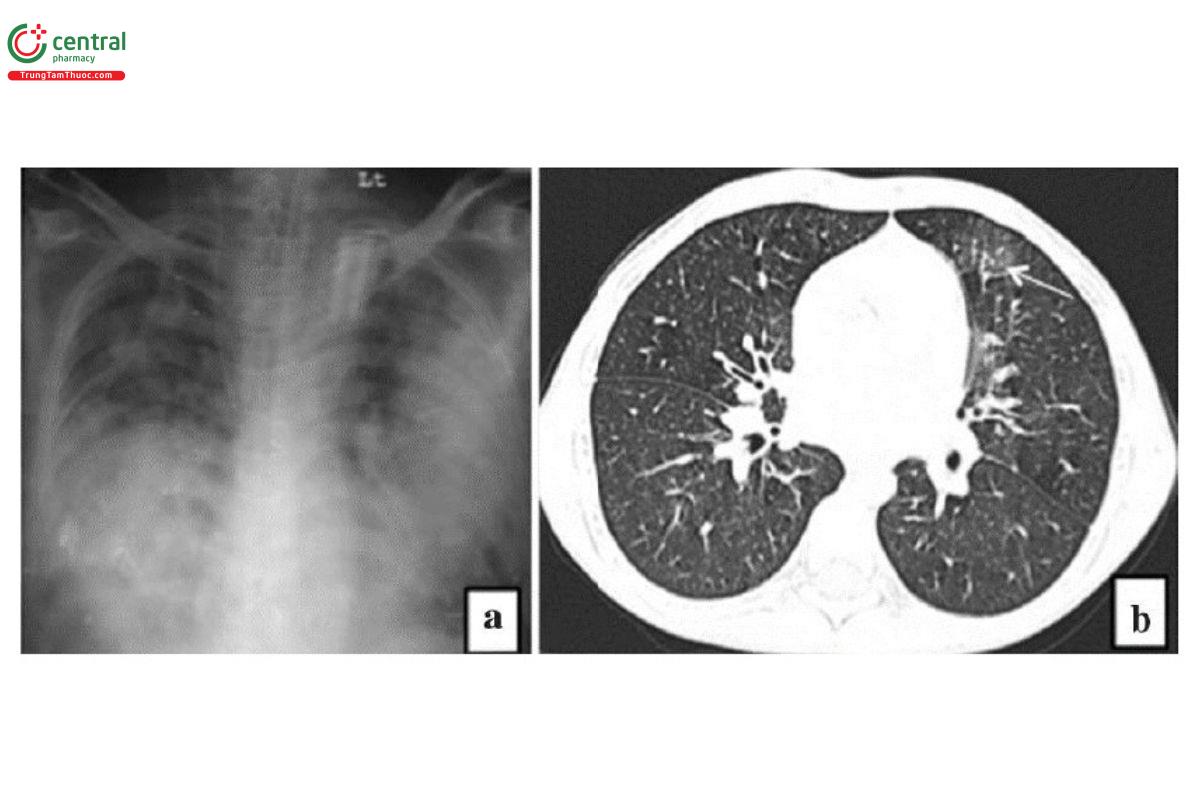

Viêm phổi do Mycoplasma pneumoniae: X-quang ngực thấy các tổn thương mờ dạng lưới hoặc đông đặc [18]. Trên CT, phổ biến là các nốt trung tâm tiểu thùy và các vùng đông đặc từ tiểu thùy đến thùy hoặc hình ảnh kính mờ với dày thành các phế quản trung tâm.

Chú thích: a) Hình ảnh mờ dạng lưới hai bên phổi (mũi tên trắng). b) Hình ảnh các đám mờ dạng kính mờ (đầu mũi tên) và các nốt mờ bờ không rõ ràng ở hai bên phổi (mũi tên trắng)